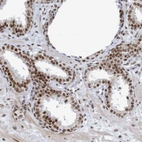

Immunohistochemical staining of human prostate shows strong nuclear positivity in glandular cells.